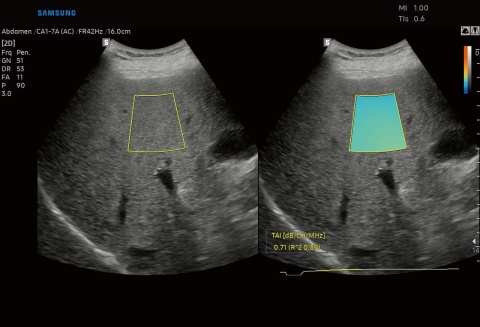

- Mit TAI (Tissue Attenuation Imaging in dB/MHz/cm) erfolgt die Quantifizierung von Steatose anhand der Messung der Dämpfung des Ultraschalls im Lebergewebe.